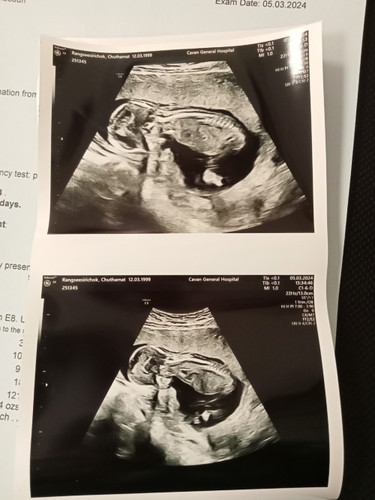

น้อง15W ไปซาวด์มาเมื่อวานน้องนอนคว่ำหน้าแบบนี้ปกติมั้ยค่ะแม่ๆบ้านไหนเป็นแบบนี้บ้างค่ะ